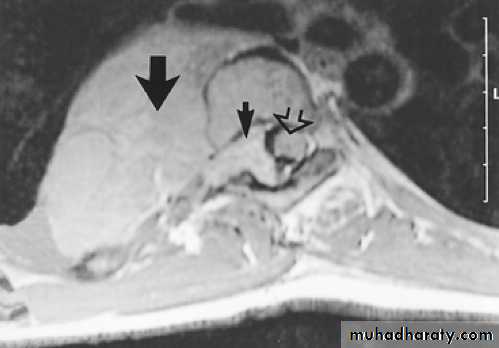

MRI: very small role in chest, but increasingly large part in cardiac and aortic dis.

Can be useful in lung CA when questions can not be answered by CT and can show intraspinal Extensions of med. Neural tumorsHorizontal fissure

Intrathoracic mass

intrasp. portionSp. cord

Neurofibroma MRI with intrasp. Extension